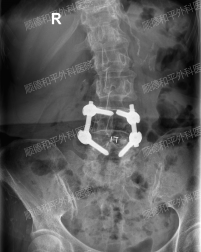

最终诊断为:“腰椎退行性变、腰椎左凸侧弯畸形、T12椎体压缩性改变、L5/S1椎间盘膨出伴真空变性、多节段椎管狭窄”等复杂腰椎病变,建议手术治疗。

手术过程中,决定采用后入L5/S1椎间盘摘除、L4/5椎间盘植骨融合内固定术治疗。在麻醉科、手术室通力配合下,不到一个小时手术顺利完成。

椎管减压非常彻底,在解除神经压迫的同时,重建了腰椎稳定性。手术创伤小、出血少,患者术后疼痛明显缓解,第二天即可在医护人员指导下下床活动,术后不到一周即达到出院标准。